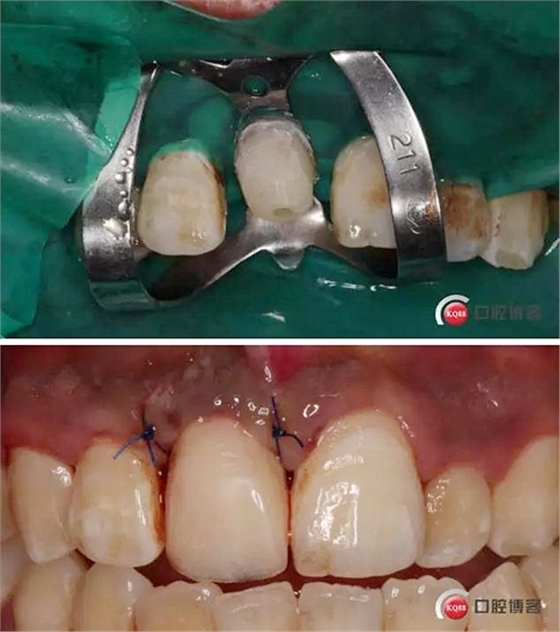

溝通后局麻下切齦,翻瓣,去骨,做冠延長(zhǎng)。翻瓣后上橡皮障 去盡繼發(fā)齲,打樁堆核,暫冠修復(fù)引導(dǎo)牙齦成型。

術(shù)后牙片可以看出樁的長(zhǎng)度有明顯增加。到達(dá)預(yù)備長(zhǎng)度。術(shù)后齦緣高度與鄰牙一致